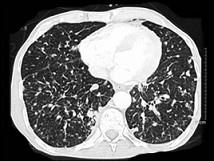

女,56岁,乳腺癌手术后,未行化疗,结合CT图像,选择最可能的诊断是 ( )A.肺转移癌B.肺结核C.间质性肺炎D.肺结节病E.肺曲菌病

问题 女,56岁,乳腺癌手术后,未行化疗,结合CT图像,选择最可能的诊断是 ( )

选项 A.肺转移癌 B.肺结核 C.间质性肺炎 D.肺结节病 E.肺曲菌病

答案 A